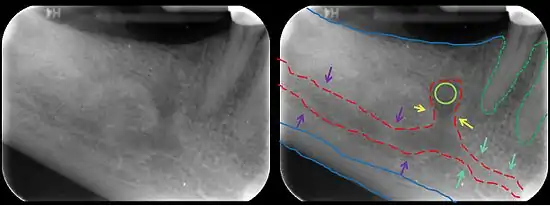

In human anatomy, the mandibular canal is a canal within the mandible that contains the inferior alveolar nerve, inferior alveolar artery, and inferior alveolar vein. It runs obliquely downward and forward in the ramus, and then horizontally forward in the body, where it is placed under the alveoli and communicates with them by small openings.

The mandibular canal is continuous with tow foramina: the mental foramen which opens in the mental region of the mandible and carried the distal fibres of the inferior alveolar nerve as the mental nerve; and the mandibular foramen on medial aspect of ramus, into which the mandibular nerve enters to become the inferior alveolar nerve. The mandibular canal often runs close to the apices of the third molar tooth, and the inferior alveolar nerve can become damaged during removal of this tooth, causing sensory disturbance in the distribution of the nerve. This is sometimes the case for the second or first molar teeth, and care must be taken during removal or root canal treatment in such cases to prevent nerve injury or extrusion of root canal filling materials.[2]

Several variations of the mandibular canal exist with varying frequency. The most common variant is the retromolar canal (~10 % of canals), whereby a branch is given off in the mandibular ramus which terminates in the retromolar region of the mandible. The retromolar canal may cause bleeding during surgery in the retromolar region such as removal of mandibular third molar teeth. Other variants include a bifid canal with a branch (~41%):[3] following the course of the main mandibular canal before re-joining it (forward or buccolingual type); terminating at the apex of a tooth, usually the molar teeth (dental type); opening as an accessory mental foramen.[4] A trifid mandibular canal variation has also been described.[5][6]